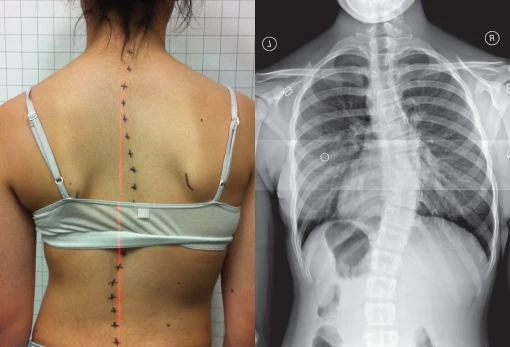

اعوجاج العمود الفقري أو ما يُعرف طبيًا بـ Scoliosis هو انحناء جانبي غير طبيعي في العمود الفقري، قد يكون بسيطًا أو واضحًا للعين المجردة.

غالبًا يظهر خلال فترة النمو السريع قبل البلوغ، أي بين عمر 9 إلى 15 سنة.

قد يلاحظ الأهل أن أحد الكتفين أعلى من الآخر، أو أن القميص لا يجلس بشكل مستقيم على الجسم.

هناك أنواع مختلفة من الاعوجاج، وأكثرها شيوعًا هو الاعوجاج مجهول السبب عند المراهقين، أي الذي لا يُعرف له سبب محدد، لكنه يرتبط بعوامل وراثية ونمو غير متوازن للفقرات.

الأطباء يعتمدون على قياس زاوية كوب (Cobb angle) لتحديد شدة الحالة:

أقل من 20 درجة: غالبًا تتابع فقط بالمراقبة.

بين 20 و40 درجة: يحتاج الطفل إلى ارتداء حزام اعوجاج العمود الفقري (Brace).

أكثر من 45–50 درجة: قد تُناقش الجراحة لتصحيح الانحناء ومنع تدهور الحالة.